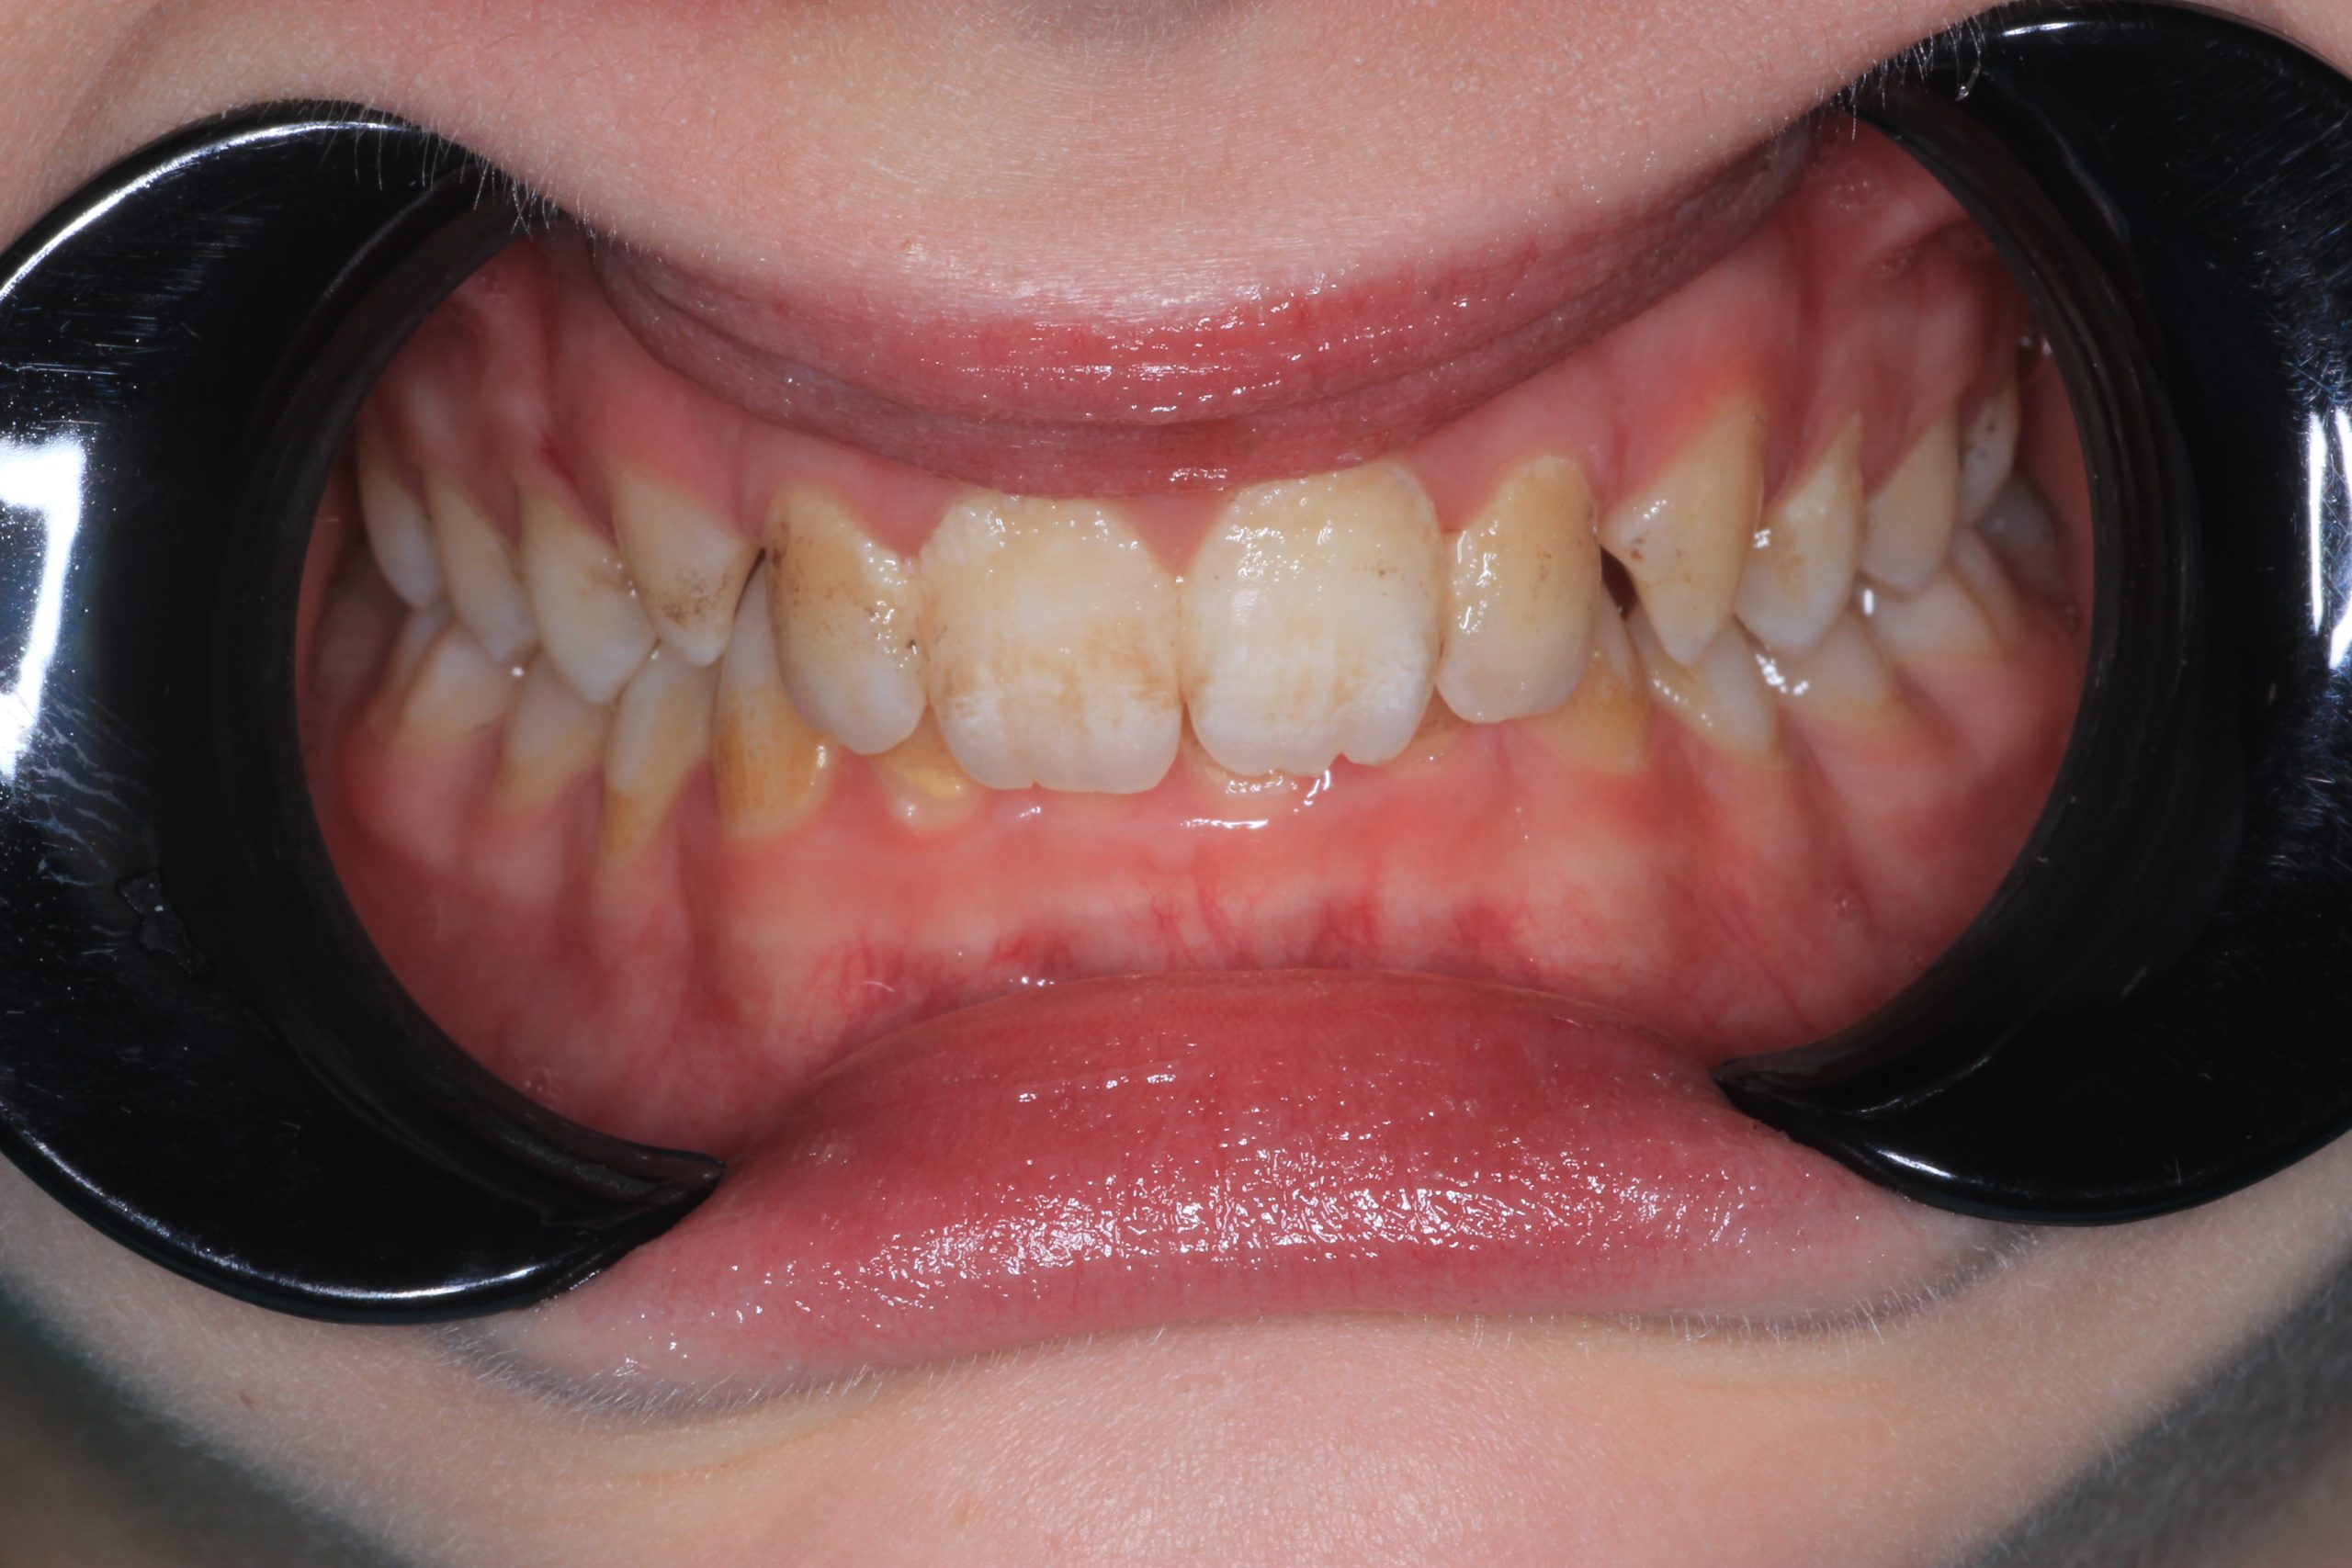

- Detailed Examination

We examine the condition of teeth, gums, and bite. - Plaque Disclosure with Special Indicators